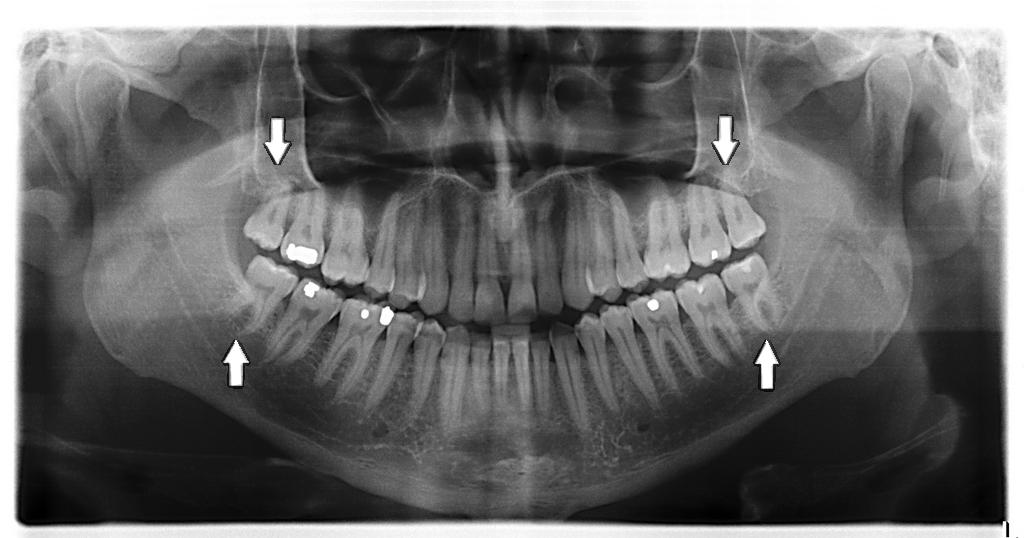

Os dentes do siso, também chamados de terceiros molares, são os últimos dentes da dentição definitiva a sair e, muitas vezes, trazem consigo problemas e dores de cabeça. Estes dentes têm a localização mais posterior de todos e a idade habitual de erupção é entre os 17 e os 21 anos podendo, em casos raros, sair muito mais tarde.

Por vezes, o dente do siso não tem espaço para sair e pode lesar os dentes adjacentes sendo necessária a sua extração.

Assim sendo, consulte o seu dentista para que este possa avaliar o seu caso e indicar o melhor plano de tratamento.